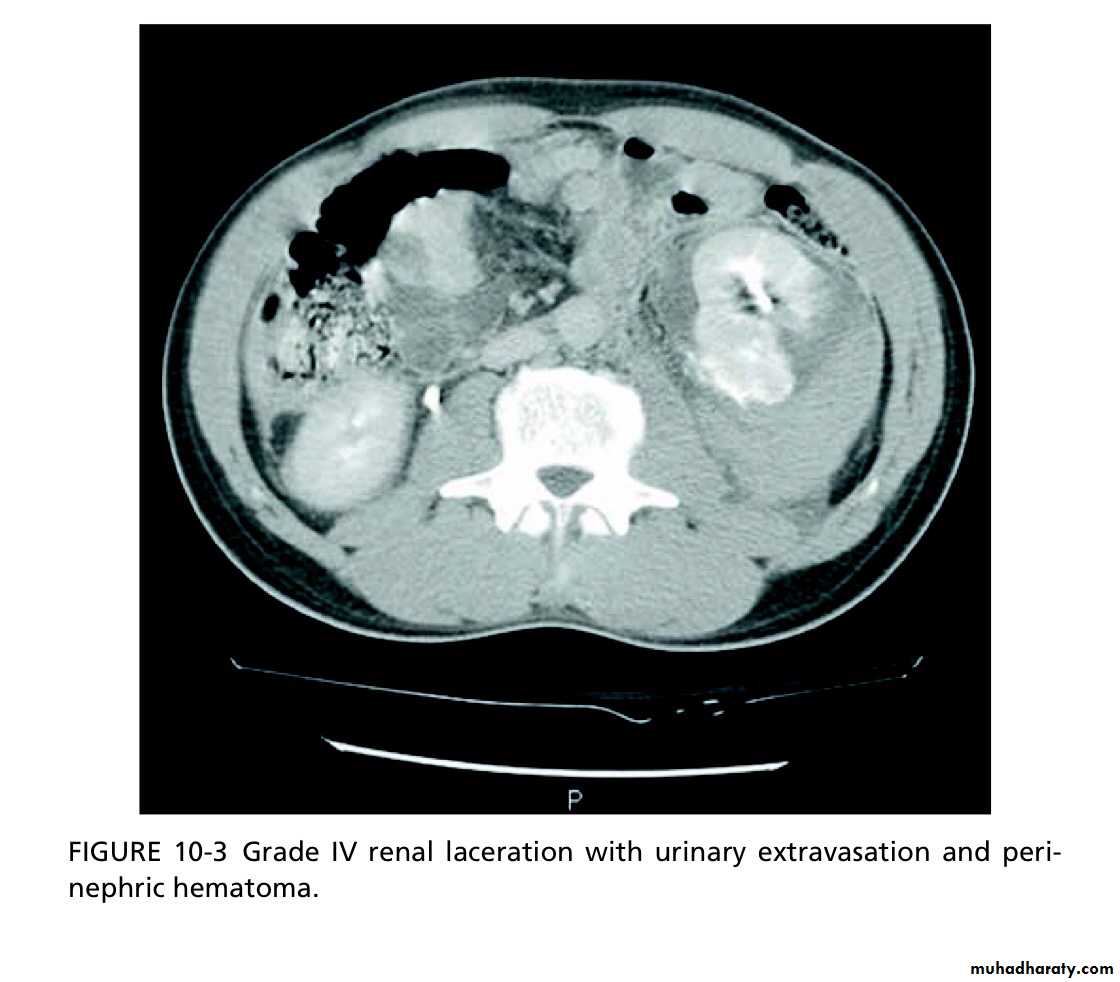

Using CT, renal injuries can be staged according to the AmericanAssociation for the Surgery of Trauma (AAST) Organ Injury Severity Scale. Higher inju- ry severity scales are associated with poorer outcomes.

Grade IV

Parenchymal laceration, involving cortex, medulla and collect- ing system OR renal artery or renal vein injury with contained haemorrhage.

Macroscopic haematuria: in a cardiovascularly stable patient, having staged the injury with CT, admit for bed rest (no hard and fast rules as to dura- tion) and observation until the macroscopic haematuria, if present, resolves (cross-match in case BP drops); give antibiotics if urinary extravasation.

High-grade (IV and V) injuries: can be managed non-operatively if they are cardiovascularly stable. However, grade IV and, especially, grade V injuries often require nephrectomy to control bleeding (grade V injuries function poorly if repaired).